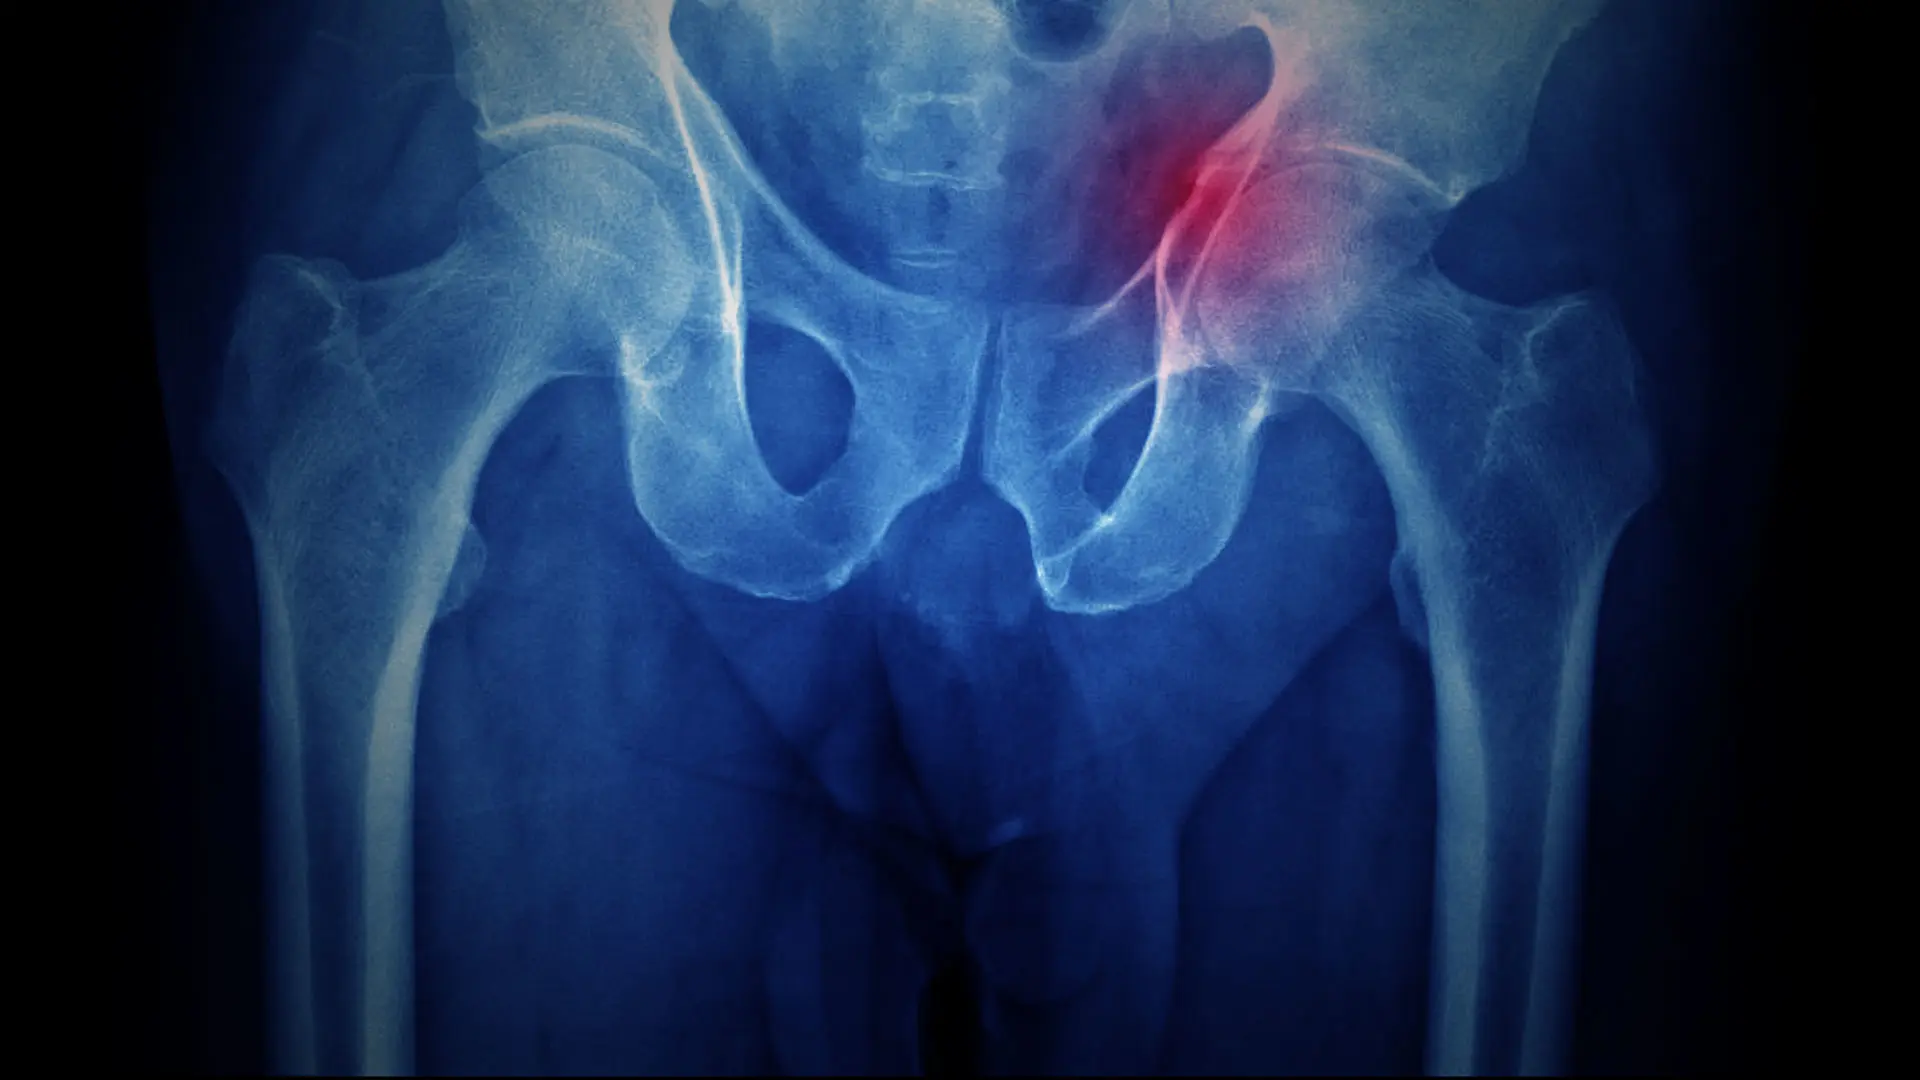

این مطالعه که در یک بیمارستان ارجاعی ارتوپدی شفا یحیائیان انجام شد، تأثیر پاندمی را بر پذیرش بیماران، اعمال جراحی و مدت بستری افراد مبتلا به شکستگی لگن بررسی کرد. برخلاف انتظارات اولیه، محققان هیچ افزایش قابل توجهی در پذیرش بیماران مبتلا به شکستگی لگن در طول پاندمی مشاهده نکردند، یافتهای که در تضاد با گزارشهایی از سایر نقاط جهان است. این مشاهده نشان میدهد که علیرغم اختلال کلی ناشی از پاندمی، افراد مبتلا به شکستگی لگن به دلیل شدت و فوریت بیماری خود به دنبال مراقبتهای پزشکی بودند.

در حالی که تعداد پذیرشها ثابت ماند، این مطالعه تغییری قابل توجه در روشهای مدیریت بیمار را آشکار کرد. بیماران مبتلا به شکستگی لگن در مقایسه با قبل از پاندمی زودتر از بیمارستان مرخص شدند و سریعتر تحت عمل جراحی قرار گرفتند. این روند غیرمنتظره ممکن است به چند عامل نسبت داده شود، از جمله اولویتبندی جریان سریع بیمار توسط بیمارستانها برای به حداقل رساندن خطر ابتلا به عفونت و صرفهجویی در منابع در طول پاندمی. علاوه بر این، پیشرفت در تکنیکهای جراحی و پروتکلهای مدیریت درد ممکن است به کاهش مدت بستری در بیمارستان کمک کرده باشد.